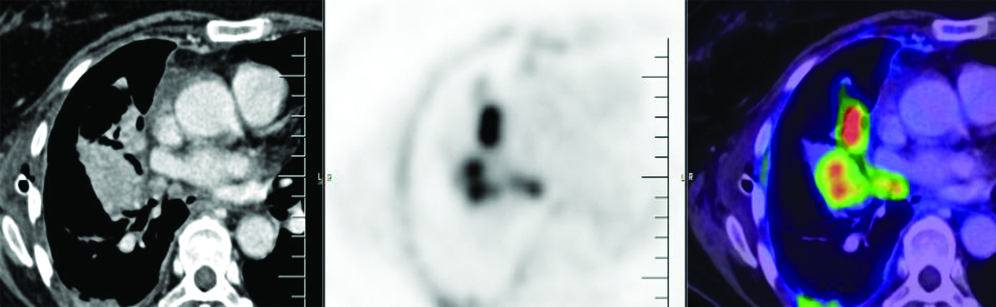

The patient underwent a 2-D echocardiogram which showed normal chambers, an ejection fraction of 63% with normal pulmonary artery pressure. PET/CT scan showed FDG avid collapse consolidation seen involving the whole of the right middle lobe and most of the anterobasal segment of the right lower lobe. Also, a relatively well-defined enhancing FDG avid lesion (Standardised Uptake Value [SUVmax] 11.9) in the collapsed lateral segment of the right middle lobe was seen, measuring approximately 4.3×2.4×2.5 mm with metastasis to the right pleura, lymph nodes, pleural deposits, liver, adrenal gland, right L5 vertebral pedicle and left iliac bone [Table/Fig-1,2 and 3].

Positron Emission Tomography-Computerised Tomography (PET-CT) scan: Well-defined enhancing Fluorodeoxyglucose (FDG) avid lesion seen (SUVmax 11.9) in collapsed lateral segment of right middle lobe, measuring approximately 4.3×2.4×2.5 mm - likely malignant lesion.

PET/CT scan: Multiple FDG avid (SUVmax 16.1) thick enhancing areas of pleural thickening seen involving most of the right pleura and fissures, the maximum thickness measuring approximately 19 mm—likely pleural metastasis.

PET/CT scan: Well-defined malignant lesion the right middle lobe of lung with metastatic lesions in the right pleura, multiple lymph nodes, right anterior extra pleural, liver, left adrenal gland, right L5 vertebral pedicle and left iliac bone.